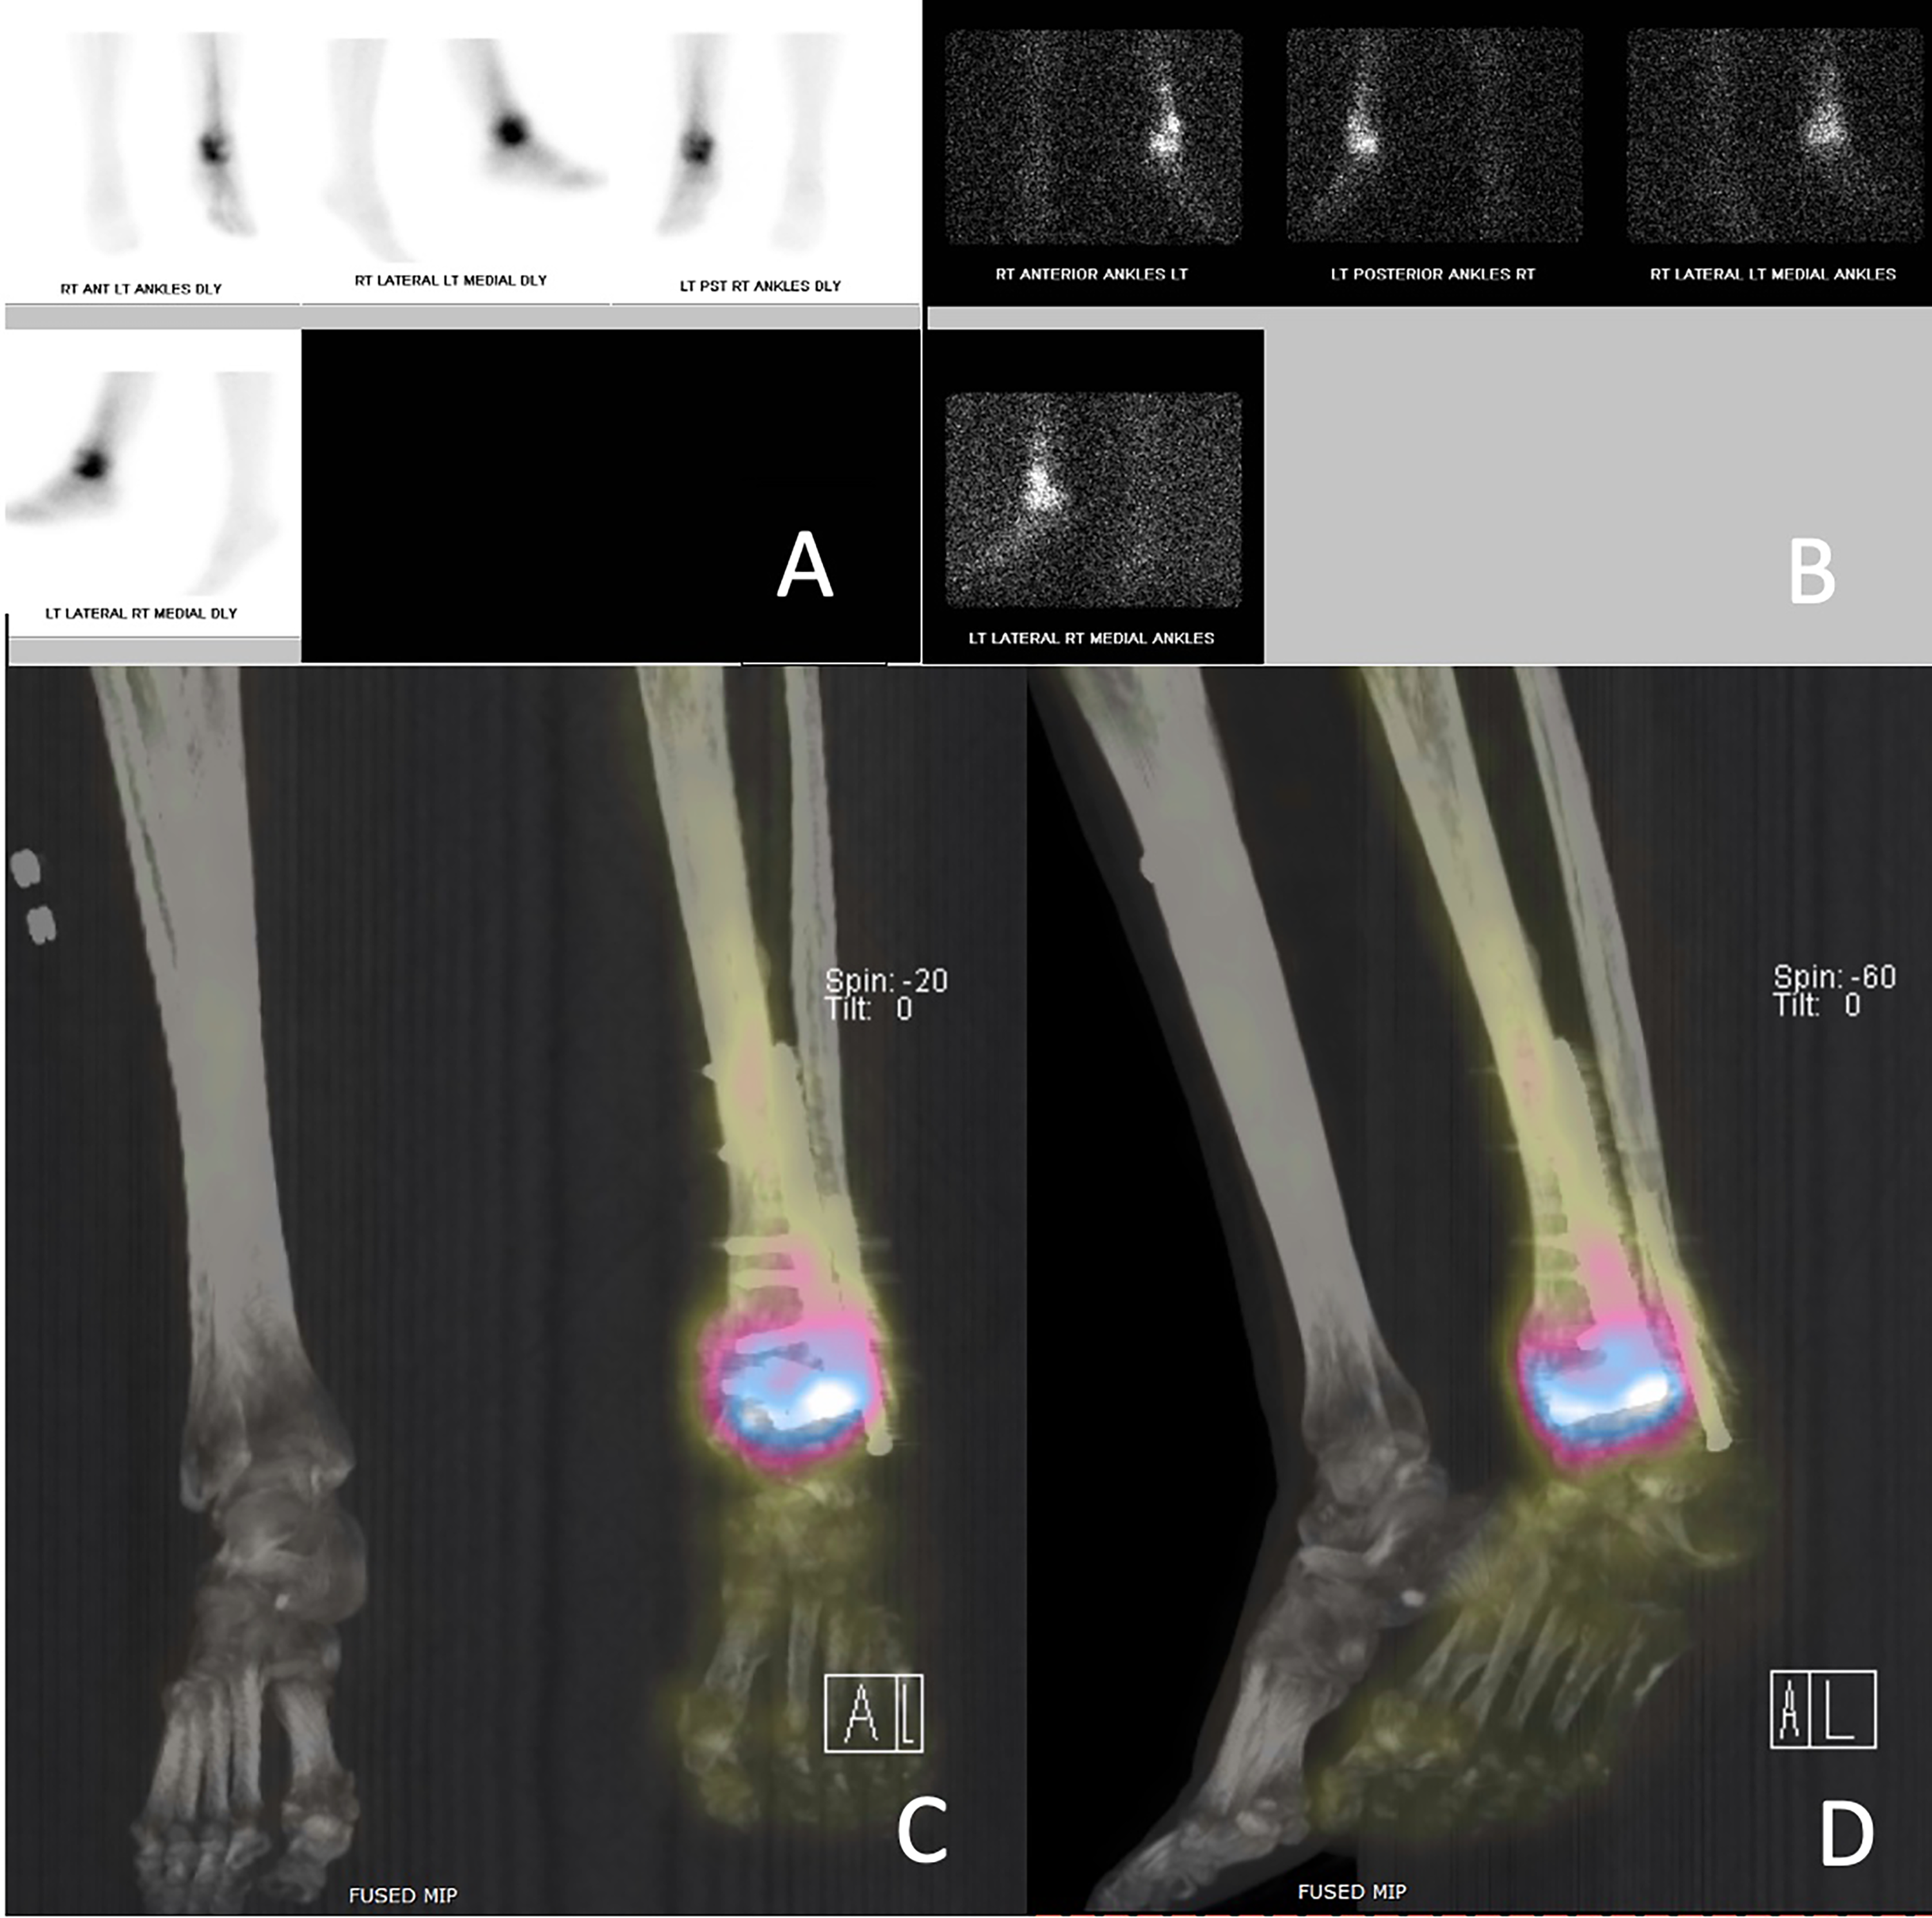

On physical examination, she was noted to be neurovascularly intact. There was nonpitting edema with a moderate joint effusion encompassing the anterior ankle. On inspection, a 10-cm cicatrix was apparent to the anterior ankle and a superficial abscess with central sinus tract noted to the anterolateral ankle (Fig. 1). Ankle range of motion was noted to be restricted with grating and crepitation present. There was tenderness to palpation of the distal tibia, fibula, and medial and lateral ankle gutters. Preoperative radiographs revealed an axial screw fixation of the fibular fracture with periosteal bone formation, as well as an anterolateral buttress plate with evidence of subsidence of the distal tibia with intra-articular screw migration to the talocrural joint (Fig. 2). The tibial fracture appeared consolidated, but hardware lucency along the metaphysis suggested chronic osteitis. Three-phase bone scan and single-photon emission computed tomography revealed focal radiotracer uptake to the left ankle suggestive of osteomyelitis (Fig. 3).

Figure 3. Three-phase bone scan with standard (A) and inverted (B) images demonstrating focal radiotracer uptake in blood flow, blood pool, and delayed imaging phases across the ankle suspicious of osteomyelitis. Anteroposterior (C) and lateral (D), SPECT imaging demonstrating maximal radiotracer uptake localized to the left ankle joint suggestive of osteomyelitis.